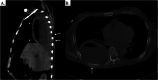

Plain chest computed tomography (CT) images. (A) Sagittal chest CT image showing dissolution of the intercostal muscles at the bedsore site (arrows) with a gravity‐dependent fluid level indicating the presence of both liquid and air. A thickened necrotic chest wall (arrowheads) demarcated the lung from the empyema cavity. (B) Axial image exhibiting osteosclerosis of the rib and an irregularity of cortical bone (arrow) as a result of inflammatory spillover.